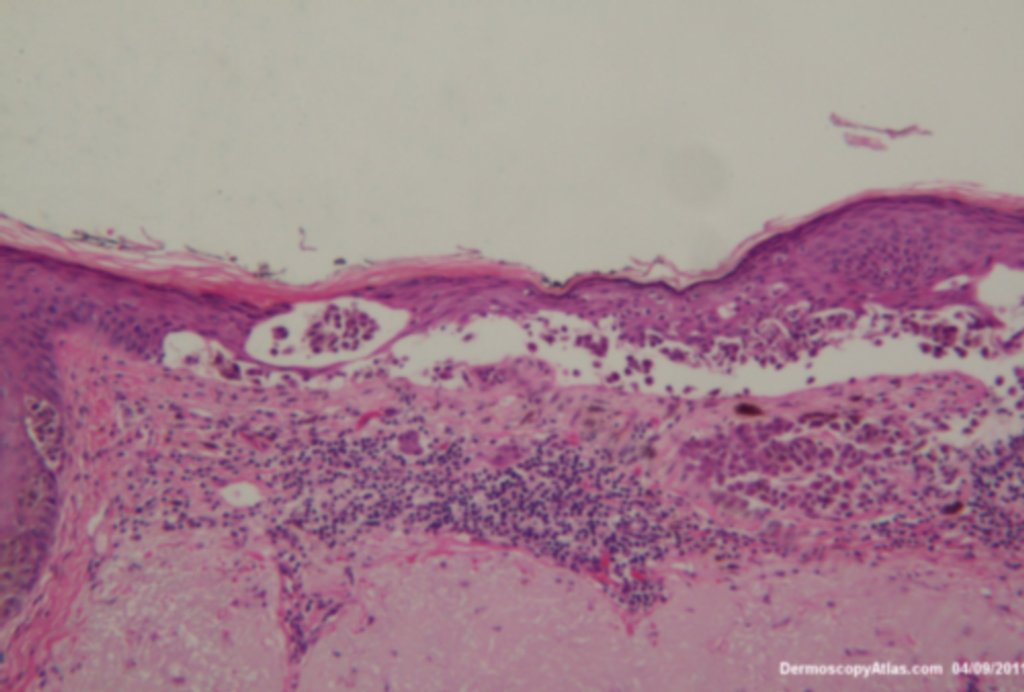

Image Number #3236 (Melanoma - Scalp location)

Diagnosis: Melanoma - Scalp location

This lesion was noted fotuitously when the patient was having another procedure done on his back. Dermatoscopically it shows peripheral clods of varying sizes, multiple colours and on the enlarged dermatoscopic view some diffuse fine grey dots. It was an invasive melanoma Level 2 , 0.4mm in depth . The histology shows an unusual feature of acantholysis of the tumour nests.